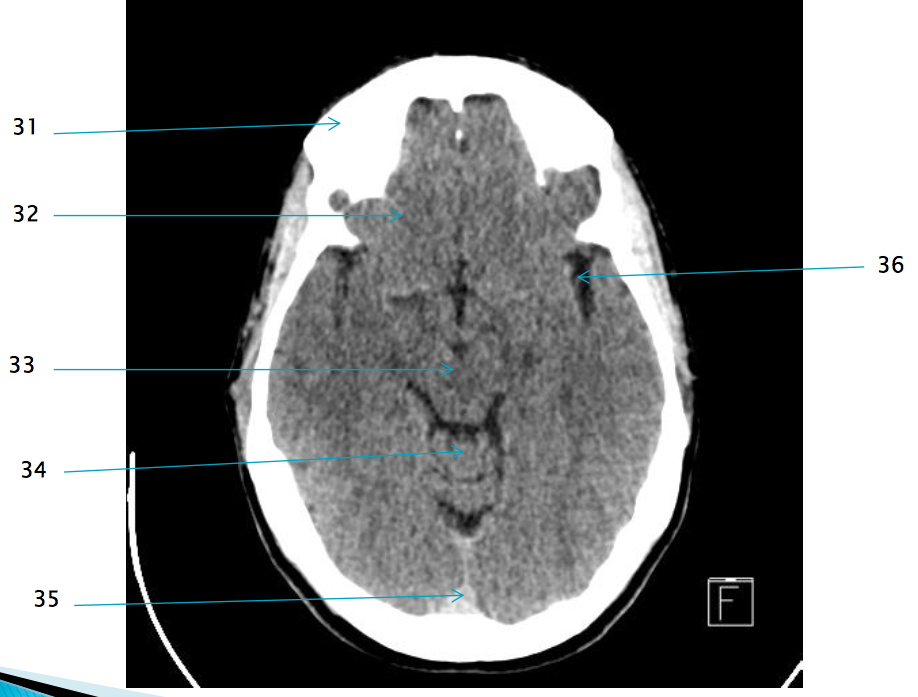

35

Superior sagittal sinus

32

R frontal lobe

37

Frontal horn of R lateral ventricle

17

internal occipital protuberance

38

Septum pellucidum